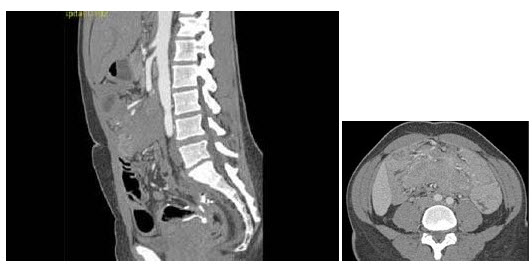

21、单项选择题

男,74岁,间歇性无痛性全程血尿2月余,尿路造影及CT平扫+增强如图所示,下列说法错误的是()

女,36岁,左侧腰痛2年余,CT检查如图所示,下列说法错误的是()

A.左肾下极可见一混杂密度病灶,边界尚清

B.左肾病灶中可见脂肪密度灶,该区增强时无强化

C.右肾中极可见一小类圆形混杂密度病灶

D.考虑为肾癌

E.考虑为双肾错构瘤